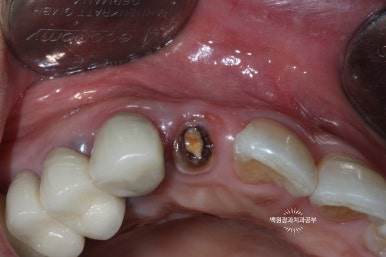

왼쪽: periotome을 사용하여 발치 시행, 오른쪽: 치아를 완전히 뽑지 않고 위치를 수정.

외과적 정출술의 핵심은

남은 치아 뿌리(잔존치근)가 부러지지 않고 온전히 탈구가 되어 나와주어야 한다는 것입니다.

이를 위해 제가 있었던 치주과에서는 페리오톰(periotome)이라는 아~주 얇은 기구를 사용하여 치아를 주변 치조골에서 분리해내어 조심스럽게 약간 빼어내곤 했습니다.

치아를 약간 정출시킨 후 봉합사를 이용하여 고정해줍니다.

보시는 바와 같이 치아를 약간 정출시켜줍니다. 대개는 2-3mm 정도 정출시킵니다.

오른쪽 사진을 보시면, 입천장 쪽에서 보았을 때 치아가 보다 더 정출한 것을 보실 수 있어요.